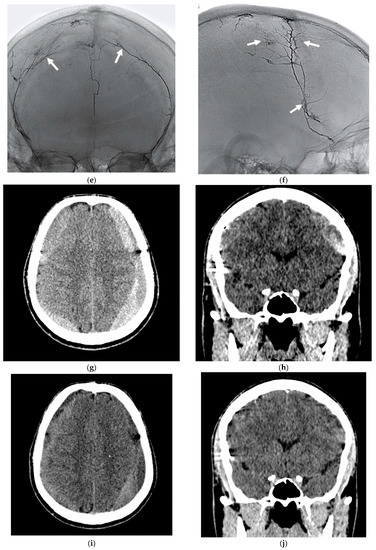

- A 70-year-old patient with left-handed CSDH and a midline shift of 12 mm, motor aphasia, and right-hand hemiparesis.

- A 42-year-old patient with bilateral CSDH that progressively increased during 1.5 months from 54 mL to 69 mL on the right-hand side and from 68 mL to 83 mL on the left-hand side, causing significant compression of both hemispheres and neurological deterioration.

- An 89-year-old patient with bilateral CSDH (no midline shift). There was no apparent connection with an antecedent head injury. However, the patient’s relatives reported that the patient did periodically fall. At the time of admission, the patient presented tetraparesis and a decreased level of consciousness.